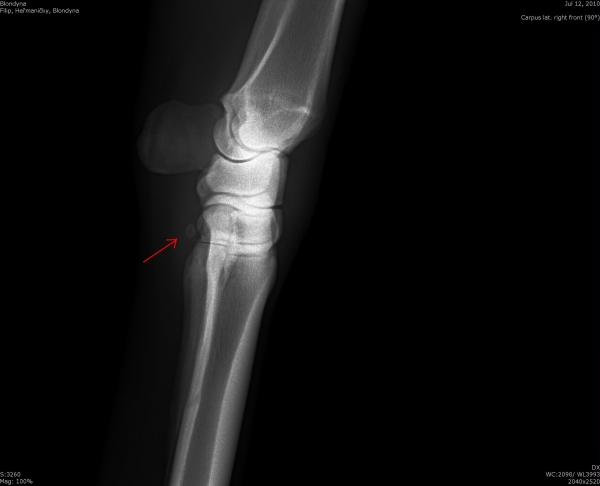

První karpální kůstka - kost, která se vyskytuje u malého % koní

Fragment na spěnkové kosti